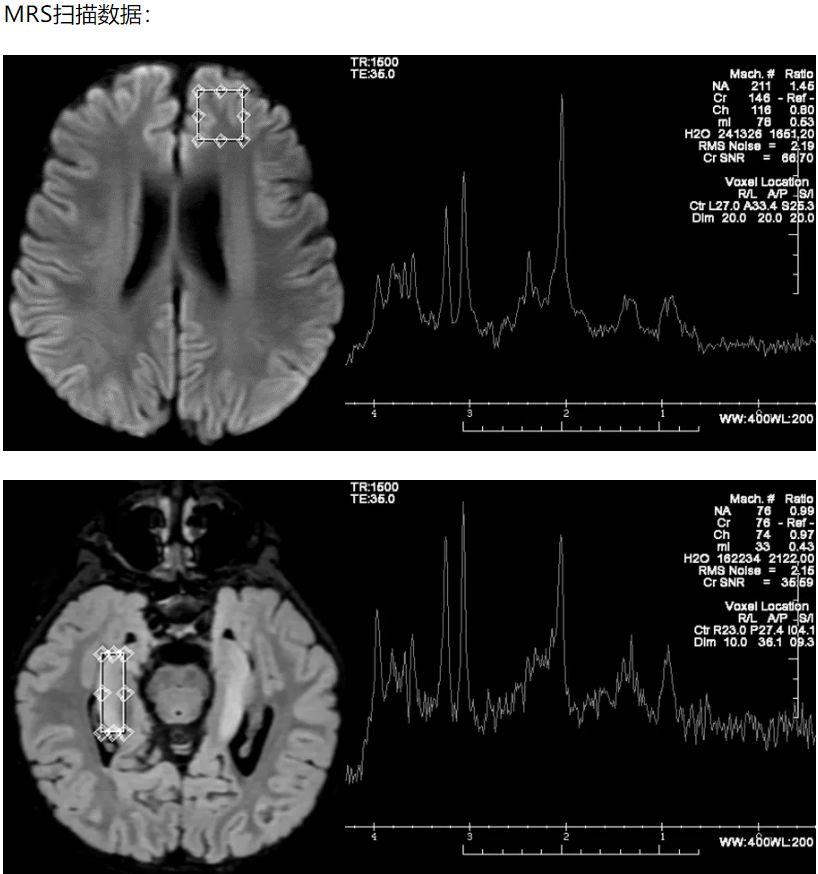

MRS一如既往地稳定,好像什么都说了,又好像什么都没说。

将额叶波谱原始数据导出,使用Lc-Model 软件进行定量分析,结果如下:

患儿Glx明显升高。在正常情况下,谷氨酸会参与神经细胞间的信号传递,但大量的谷氨酸堆积会改变涉及计划和决策的脑区——外侧前额叶皮层(lPFC)的性能。

- 癫痫发作导致兴奋性氨基酸(Glu)升高,Glu有毒性作用,导致弥散受限表现。胶质细胞对Glu进行解毒,降解为无毒性作用的谷氨酰胺(Gln)。由于Glu和Gln主体分子结构相同,所以MRS并不能严格区分二者,统称为Glx。